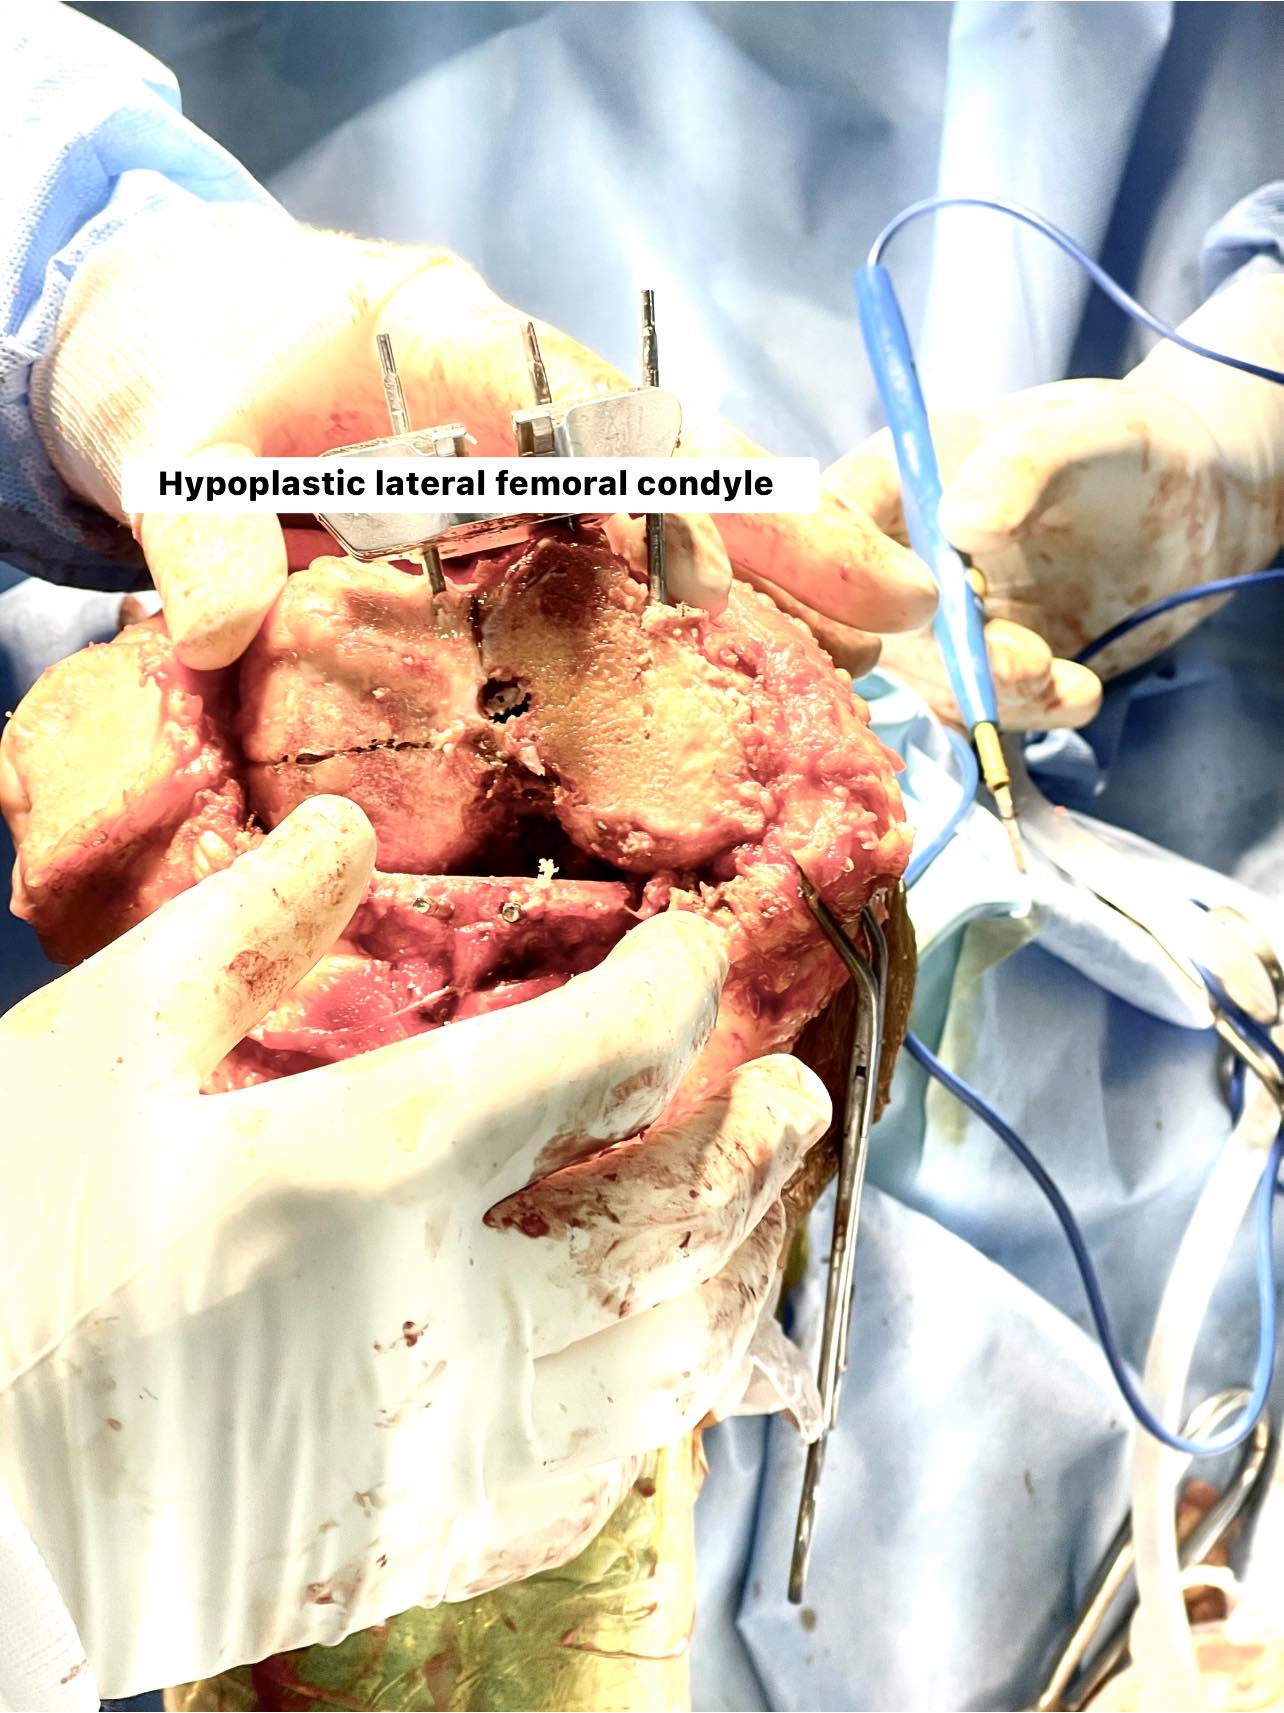

48-year-old male with windswept deformity of knees due to rheumatoid arthritis, both femoral lateral condyles are hypoplastic. Left tibia has a medial bone defect of 20 mm. Treated with long stem prostheses for tkr (total knee replacement) with semi-constrained liners. For the left knee bone defect, bone grafting was done with cc screw fixation.

In such extensively damaged knees it is important to keep all options in hand and pre-plan properly preferably on the computer to give optimum result.